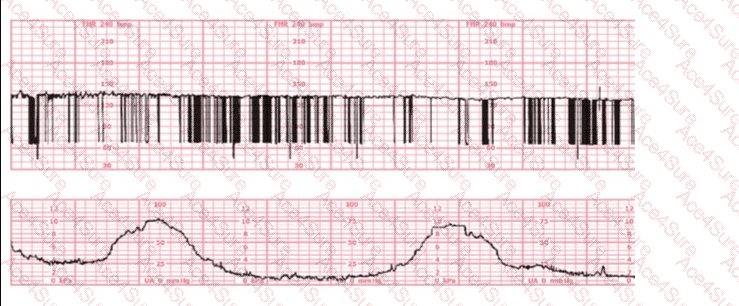

When evaluating an admission tracing, NCC emphasizes determining whether the pattern represents baseline variability abnormalities, signal artifact, or an underlying fetal cardiac rhythm disturbance. The strip shown contains clear features of a fetal dysrhythmia, which NCC and AWHONN describe as an irregular rhythm characterized by inconsistent R–R intervals or intermittent missed beats.

Key features in this tracing:

Extremely irregular FHR signalThe pattern shows abrupt vertical spikes, inconsistent spacing, and intermittent loss of coherent waveform. NCC teaches that this appearance is typical of irregular ventricular conduction or premature atrial/ventricular contractions.

Wide variability in beat spacingBeat intervals vary significantly, suggesting ectopic beats or conduction abnormalities rather than a stable rhythm such as heart block or atrial flutter.

Sensor not malfunctioningThe lower uterine activity channel is smooth and consistent, meaning the upper channel’s abrupt changes represent true FHR signal irregularity, not artifact.

C. Fetal dysrhythmia – CORRECT

NCC, AWHONN, Miller, and Menihan describe fetal dysrhythmias as:“Irregular, inconsistent FHR patterns due to premature atrial contractions (PACs), premature ventricular contractions (PVCs), or intermittent conduction disturbances.”

The hallmark is an irregular rhythm, often appearing as abrupt spikes or missing beats on the monitor.

The tracing shown matches these characteristics precisely.

Therefore, the tracing is most consistent with fetal dysrhythmia, typically benign PACs/PVCs, and is the correct answer.